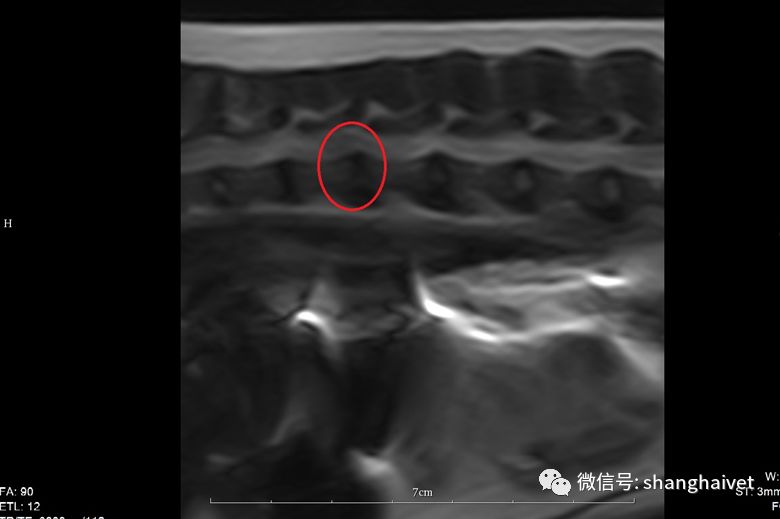

▲MRI扫描显示T12-T13椎间盘信号下降,有突出,且压迫脊髓

进一步的核磁检查显示T12-T13段椎间盘T2信号降低,有较明显的椎间盘突出,压迫脊髓硬膜囊。脊髓本体信号轻度增强,横断面见突出物偏右侧对脊髓造成较明显的压迫。

▲T12-T13横断面 右侧椎间盘突出压迫脊髓